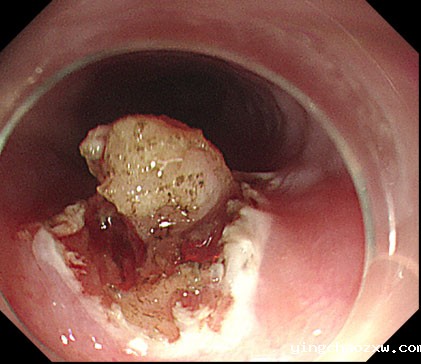

平滑肌瘤内镜下剥离术

内镜下剥离术